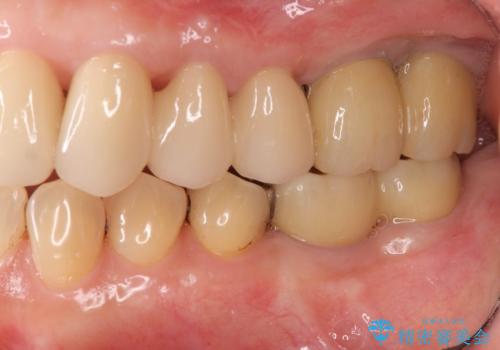

歯周病に対する全体治療

治療期間はかかりましたが、しっかりと歯周病治療・インプラント治療を行ったおかげで歯周病の状態は非常に良くなり、安定した咬合関係を確立することができました。